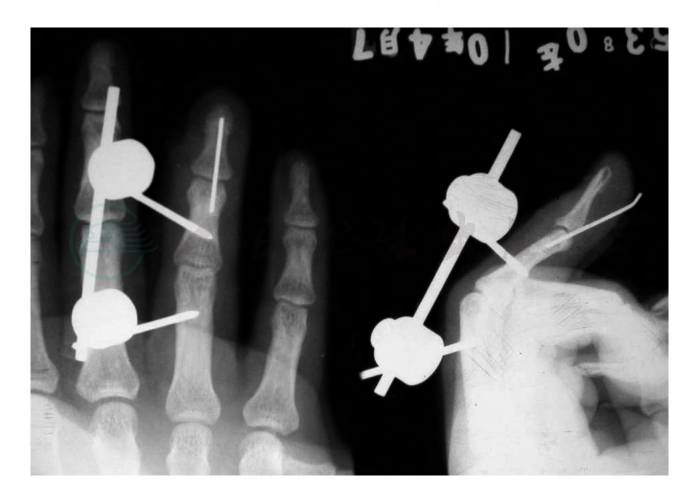

给予门诊手术治疗。手术中常规背侧Z形切口,见伸肌肌腱止点处瘢痕愈合。常规切除部分瘢痕,被动伸直远节指骨,行指骨钢针固定; 而后,将指骨远节置于过伸位,近侧指间关节置于屈曲位,在远、近节指骨桡背侧各穿1枚骨针,行指骨外固定架固定(图2)。

图2 术后X线片